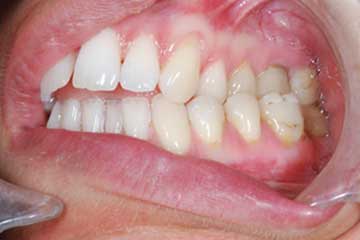

Riabilitazione gnatologica, ortodontica ed estetica

Durata del trattamento: un anno